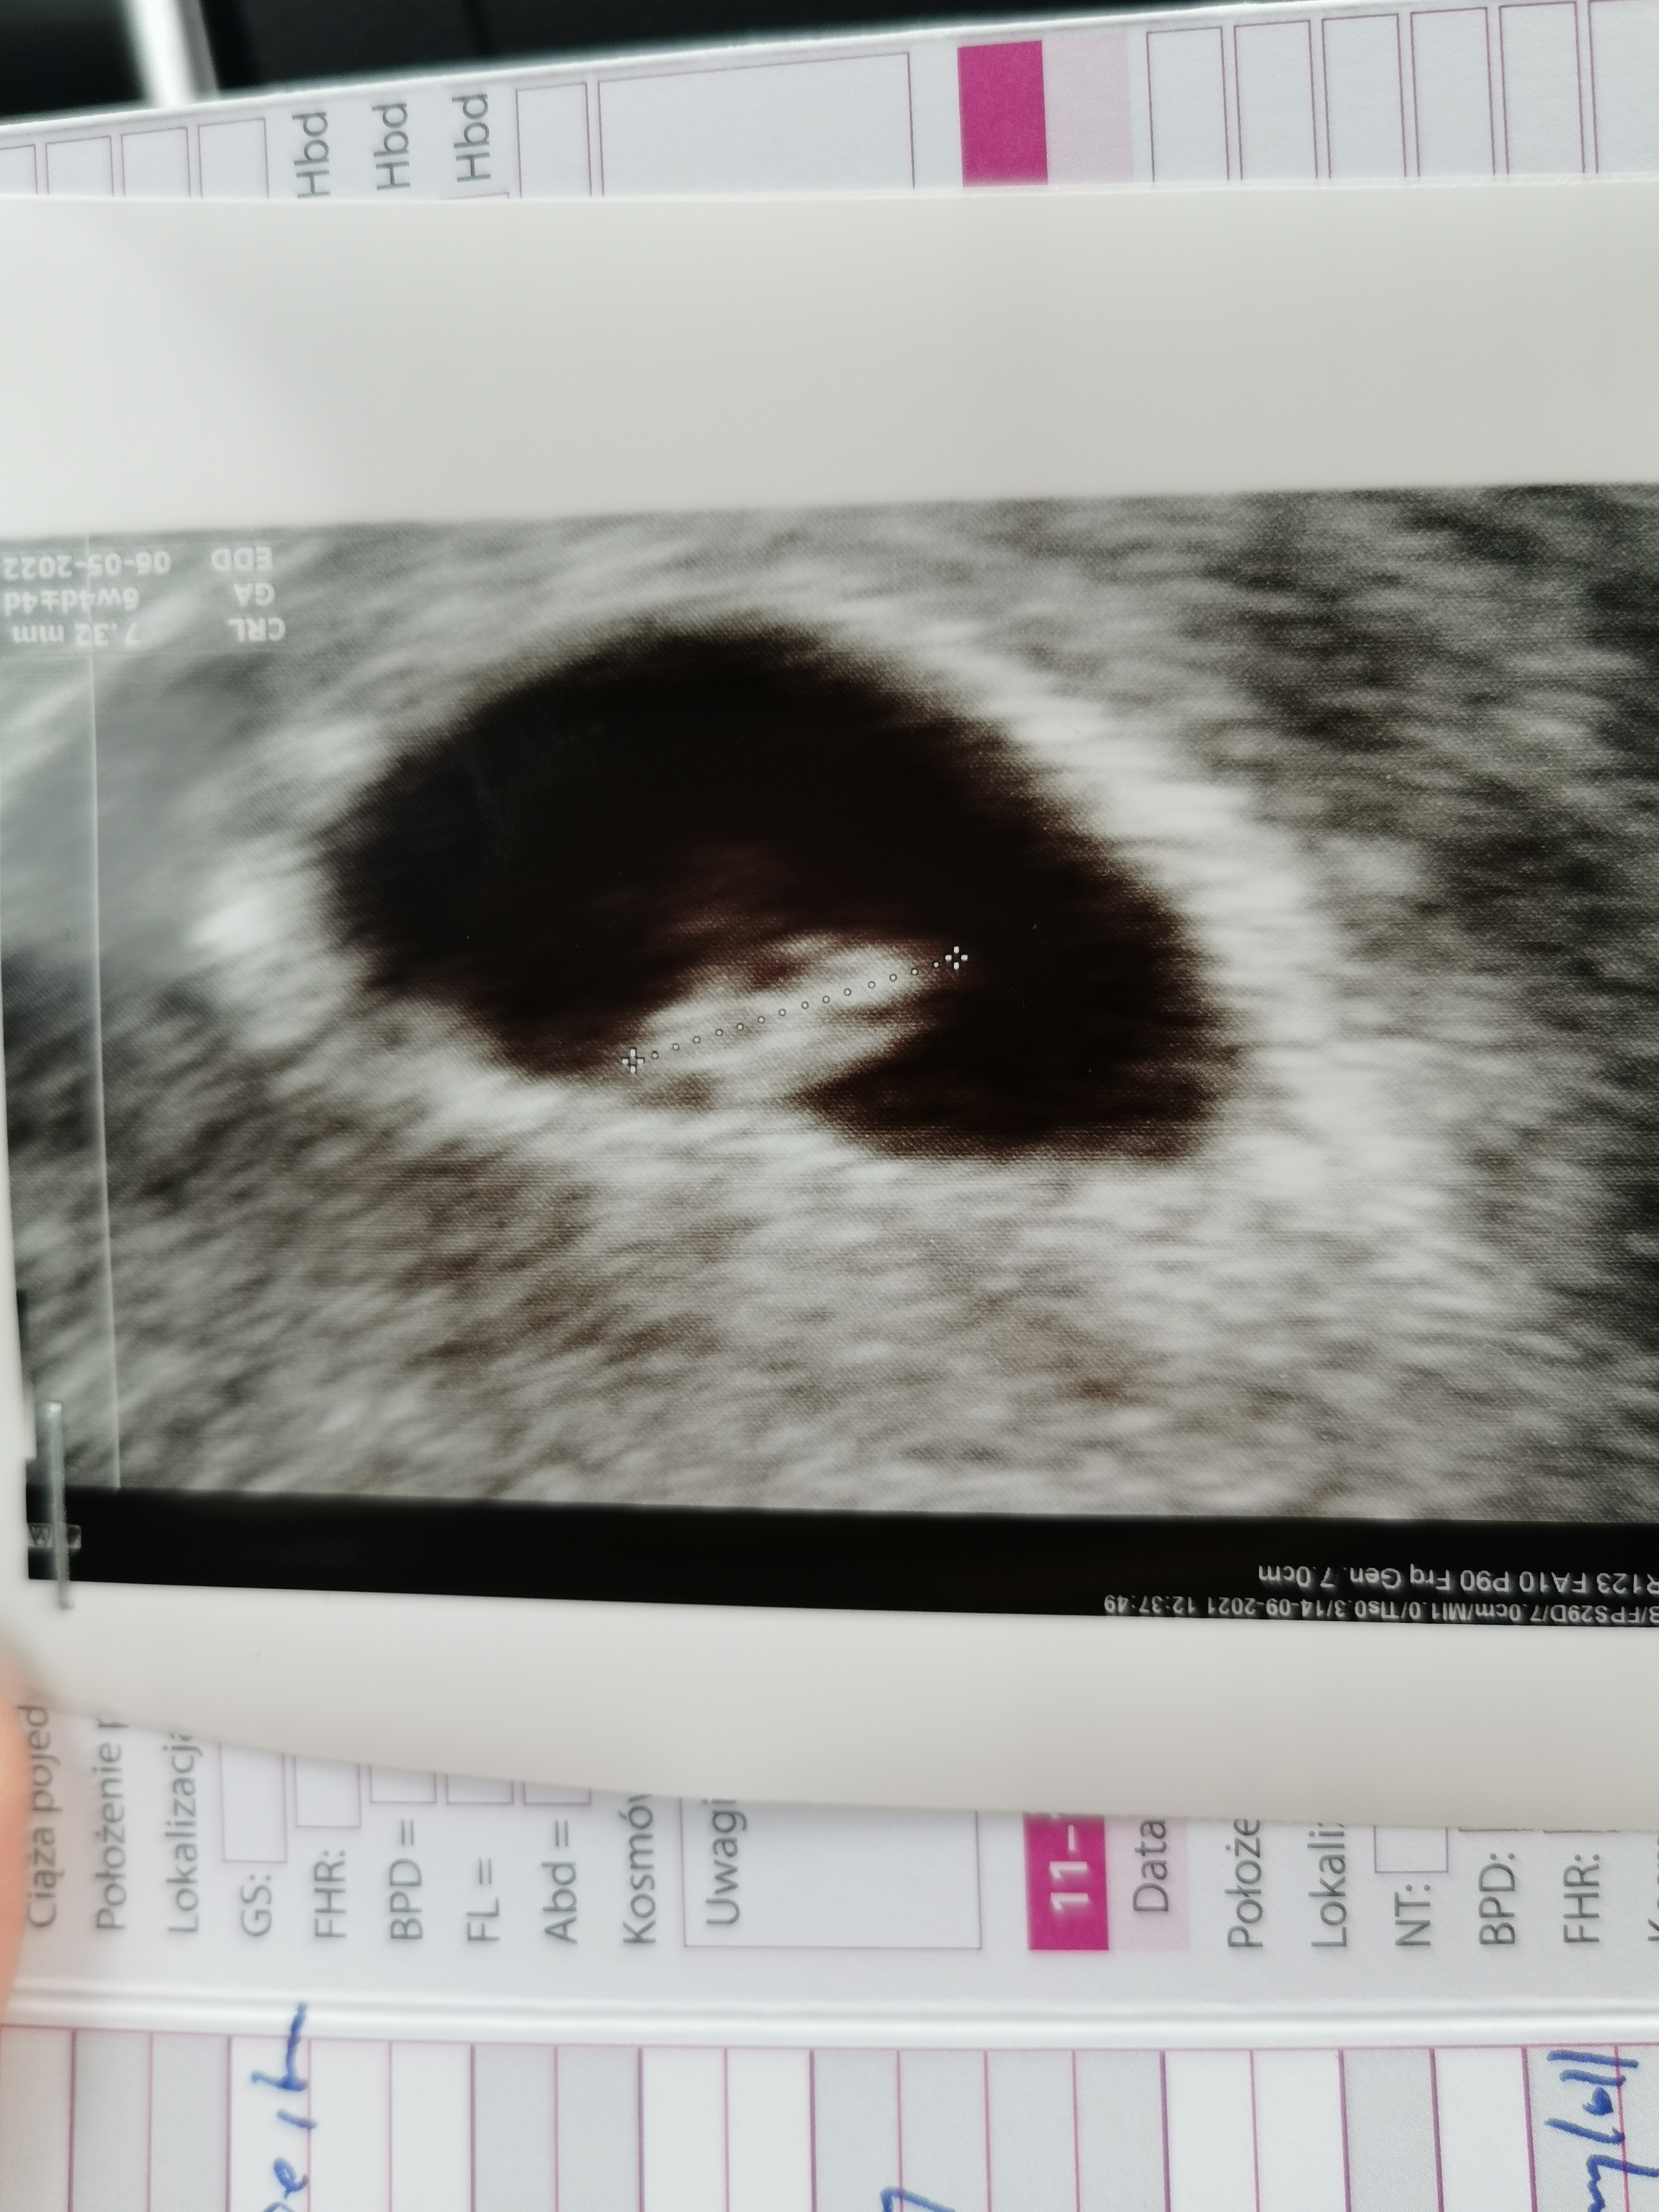

Jestem po 😉 7 tydzień serduszko bije wszytko jest ok 😍 ja do endokrynologa bo za wysokie tsh i na następną wizytę za 3 tyg obciążenie glukoza bo w poprzedniej ciąży miałam cukrzycę... Z mężem mamy ryzyko konflikt serologicznego ale badania ok przeciwciał nie wykryto 😍

Załączniki

• IMG_20210914_140207.jpg

IMG_20210914_140207.jpg

1,3 MB · Wyświetleń: 95